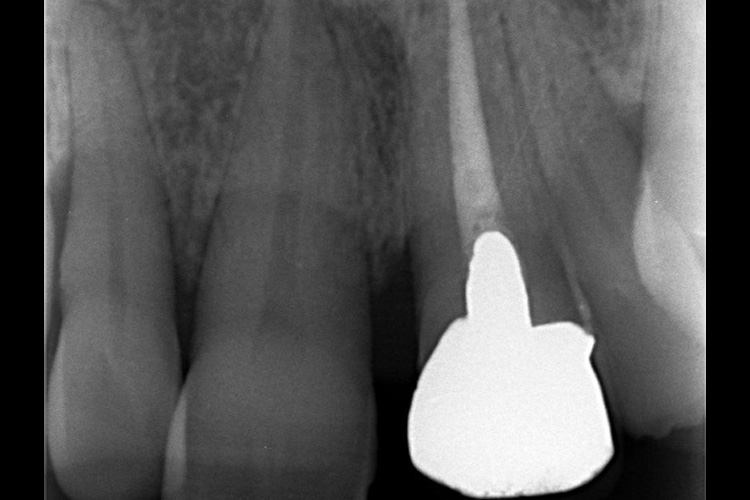

施術前のレントゲンと口腔内写真です。施術前にプラークの除去を行ってから、施術します。

施術前のレントゲンと口腔内写真です。